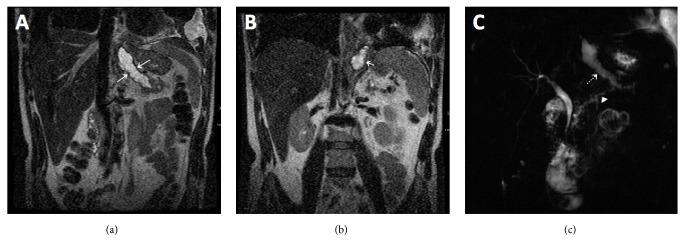

A 49-year-old male with history of chronic alcohol-induced pancreatitis presented with one month of worsening left pleuritic chest pain and shortness of breath. Chest radiograph demonstrated bilateral pleural effusions. Thoracentesis revealed increased amylase in the pleural fluid. Computed tomography (CT) and magnetic resonance cholangiopancreatography (MRCP) showed a fistula tract between the left pleural cavity and pancreas which was confirmed on endoscopic retrograde cholangiopancreatography (ERCP). Patient was treated with placement of a pancreatic stent with complete resolution of the fistula tract approximately in 9 weeks. A systematic literature search was performed on reported cases with pancreaticopleural fistula (PPF) who underwent early therapeutic endoscopy within the last 10 years. Imaging modalities, particularly CT and MRCP, play essential role in prompt preprocedural diagnosis of PPF. Early therapeutic ERCP is an effective and relatively safe treatment option for PPF, so invasive surgery may be avoided.